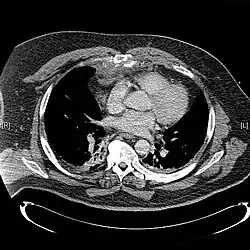

Сверху: грудина окрашена цветом морской волны. Внизу: компьютерная томограмма оскольчатого перелома грудины.[1] Сверху: грудина окрашена цветом морской волны. Внизу: компьютерная томограмма оскольчатого перелома грудины.[1] | |